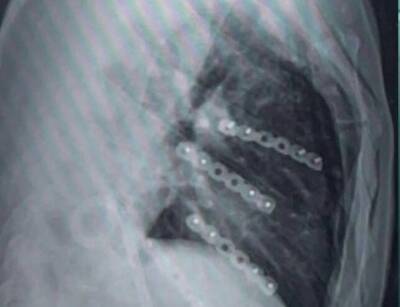

一位33歲因車禍造成右側肋骨第4、5、6、7節多處斷裂,屬連枷胸的患者,過去都未有人使用達文西手臂手術,若用傳統手術多從側胸劃開15至20公分傷口進行手術,若是內視鏡微創手術,內視鏡難免出現不穩與視角的侷限,而患者自費由澄清醫院中港院區胸腔外科主任杜承哲則用台灣創新連枷胸達文西手臂手術的術式,成功完